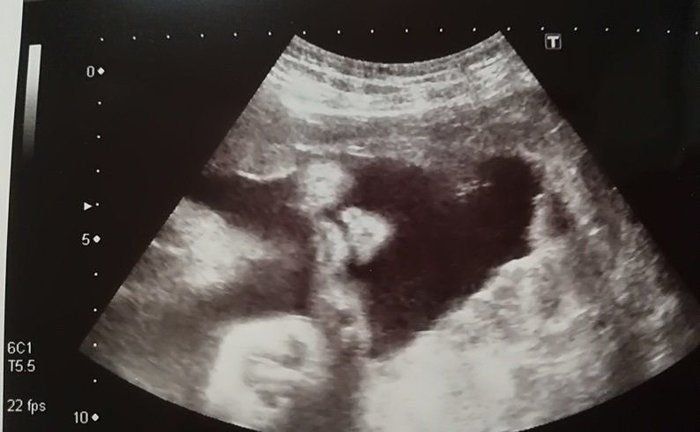

チャーミー小結さんの妊娠30週目のエコー写真

口をキュッとつぐむ様子も愛おしい表情。この頃は便秘がひどく、「酸化マグネシウム」を医師に処方してもらいました。この頃は安静にしながらも、週に1回催される母親学級へ車椅子で通い勉強していました。